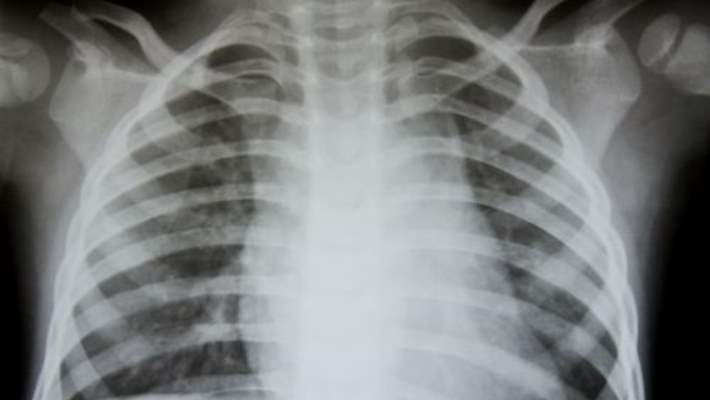

Zatürre, kişileri çok hasta edebilecek bir akciğer enfeksiyonudur. Öksürebilirsiniz, ateşiniz çıkabilir ve nefes almakta büyük güçlükler çekebilirsiniz. Birçok insanda, zatürre evde tedavi edilebilir. Hastalar, genellikle 2 ila 3 hafta arasında iyileşir. Fakat yaşlılar, bebekler ve başka hastalıkları olan insanlar daha uzun süre hasta olabilir veya hastaneye yatmaları gerekebilir.

Doktorunuz size belirtileriniz hakkında sorular sorar ve sizi fiziksel muayeneye tabi tutar. Kan testi veya röntgen isteyebilir. Bunlar normalde doktorunuzun zatürre teşhisi koyması için yeterlidir. Ancak belirtileriniz kötüyse, yaşlıysanız veya diğer sağlık sorunlarınız varsa başka testlere de ihtiyacınız olabilir. Genel bir kural olarak ne kadar hastaysanız o kadar çok test yaptırırsınız.